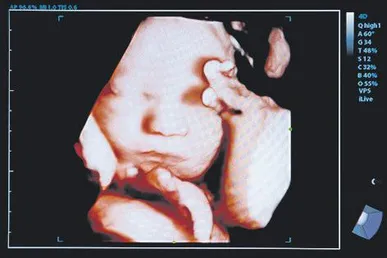

Pro-life account blocked

The March for Life UK account on social media platform X, used to organise the anti-abortion protest, was locked just days before the event.

A screenshot shared by organisers showed X had banned the account for “graphic violence or adult content." However, the content in question was a photo of an unborn child in the womb, and had already been on the account for months.